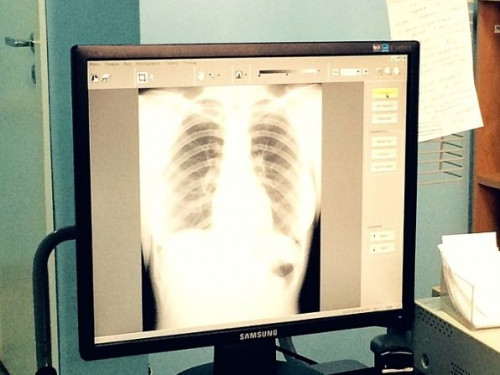

Провести эту субботу с пользой. Поликлиника на Уральской приглашает 15 сентября на диспансерные обследования

Магнитогорск. Диспансерные субботы организованы специально для удобства работающих по пятидневке горожан.

В этот день с 9 до 12 часов сотрудники поликлиники выходят специально для тех, кто не успевает на диспансеризацию в будни. Работают лабораторная и диагностическая службы, терапевты и медсёстры. Как уточняет заведующая поликлиникой №1 Юлия Гаврилкина, суббота – идеальный вариант, потому что всё организуется только для диспансеризации.

В поликлинике завтра, 15 сентября, с 9 до 12 часов ждут магнитогорцев от 21 года. Прийти может любой человек, независимо от места регистрации или проживания.

Напоминаем, что в 2018 году обследования проходят граждане, возраст которых совпадает с одним из перечисленных: 21, 24, 27, 30, 33, 36, 39, 42, 45, 48, 51, 54, 57, 60, 63, 66, 69, 72, 75, 78, 81, 84, 87, 90, 93, 96, 99 лет.

Чтобы результаты анализов крови были достоверны, нужно прийти натощак. Другая подготовка не требуется. С собой взять паспорт и медицинский полис.

Больше подробностей по диспансеризации и её особенностям – на сайте ГАУЗ «Городская больница №2»

или по телефонам регистратуры поликлиники 22-09-85 и 23-11-31.